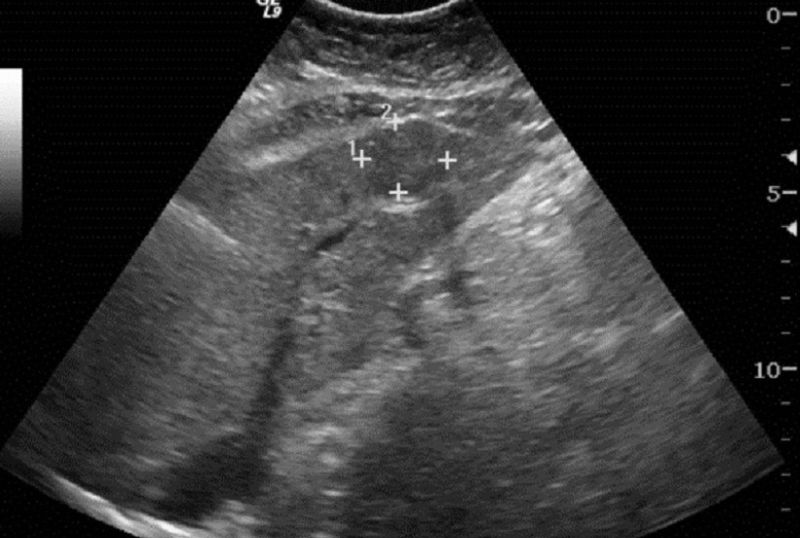

.jpg)

Siêu âm là pháp tầm soát đầu tay, không xâm lấn, chi phí thấp

Siêu âm: Là phương pháp tầm soát đầu tay, không xâm lấn, chi phí thấp. Độ nhạy dao động 68–87%. Tuy nhiên, kết quả phụ thuộc nhiều vào người thực hiện và thể trạng bệnh nhân, đặc biệt giảm ở người béo phì hoặc khối u nhỏ.